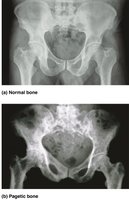

Paget’s Disease

Excessive, disorganized bone remodeling; high ratio of spongy to compact bone.

Common in spine, pelvis, femur, skull; cause unknown, possibly viral.

Treatment: bisphosphonates, calcitonin.